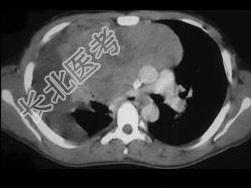

- 单项选择题女,34岁, 咳嗽,咯血半月余, 请结合影像学检查,选出最可能的诊断 ( )

A、纵隔畸胎瘤

B、淋巴瘤

C、胸腺瘤

D、神经源性肿瘤

E、肺癌